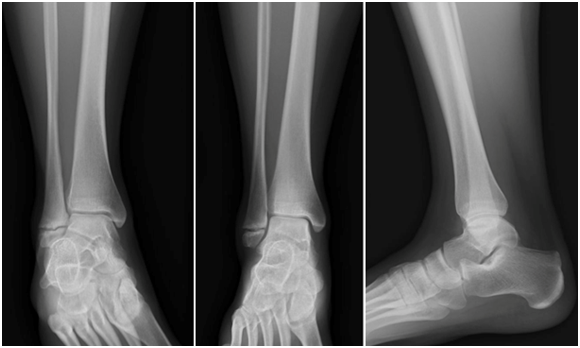

The patient was non-weight bearing in an immobilizing boot for 6 weeks and followed a normal post-operative course, with serial radiographs. The patient continued use of the bone stimulator. At 6 weeks post-operatively, the patient was allowed to begin weight bearing. At final radiographs in December 2015, a complete union was noted (Figure 3). The patient returned to all pre-injury activities without reservation. At one-year out from surgery, the patient is doing well with no complaints or limitations to activity.

Figure 3 Post-operative radiographs. Anterior-posterior, Mortise and Lateral views of the right ankle. December 2015.